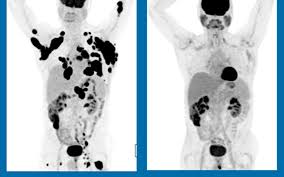

Cancer Remission What It Means What To Expect How To Plan For It from post.healthline.com A pancreatic cancer patient goes into remission if exams and tests no longer show signs of the disease. Remission is possible with stage 3 lung cancer. It is difficult to determine the expected remission of all cancer patients because there are so many variables in each case. A complete remission means that doctors see no evidence of cancer when they examine a patient and take scans, said dr. Being in remission indicates a measurable improvement of your cancer diagnosis. So you've been through cancer treatment and your doctor has called you in for some good news. What does cancer remission mean? If your doctor tells you your cancer is in remission, it often means there is a decrease in or disappearance of the.

My Cancer Is In Remission Does This Mean I M Cured from images.theconversation.com Remission can be partial or complete. Remission means that the signs and symptoms of your cancer are reduced. What's the range of survival times for people in my situation? Remission of cancer refers to the absence of active disease for a period of at least 1 month. Another common term used is complete remission, meaning basically the same thing: So you've been through cancer treatment and your doctor has called you in for some good news. Your cancer is in complete remission when, after treatment, no cancer can be detected. But what does it mean for cancer to go into remission?

Being in remission indicates a measurable improvement of your cancer diagnosis. Cancer remission is often thought to mean that the cancer has been cured. Is the cancer gone forever? After your cancer treatment has ended, the word remission may be music to your ears. Cancer remission is when the signs and symptoms of cancer have lessened or are undetectable. Remission is possible with stage 3 lung cancer. Cancer remissions are often classified as either partial or complete. a partial remission or partial response signifies a reduction of at least 30% of a not every patient will be told they're in remission. A pancreatic cancer patient goes into remission if exams and tests no longer show signs of the disease. Doctors have not found any indication that cancer remains. So remission (complete) is caused by the destruction of enough cancer cells to eliminate any observable evidence of the cancer (by physical exam, imaging studies, blood tests, etc. First, understand that oncologists use the word cure to mean a. Learn what this means and how improved treatments are helping more people reach this goal. Remission means that the signs and symptoms of your cancer are reduced.

Prophylactic Cranial Irradiation For Patients With Small Cell Lung Cancer In Complete Remission Nejm from www.nejm.org Ned means no evidence of disease and is the same as remission in that all examinations and scans have shown you to be free of cancer. Learn more about cancer remission and how the healthcare team watches for any signs of recurrence. However, the nonexistence of the active illness does not mean that there are entirely no noticeable signs of cancer or that the disease has been treated. Is it the same as a cure? You can still have cancer cells somewhere in your body. Here, four women, who've been in remission for different amounts of time share what life is like after cancer. Your cancer is in complete remission when, after treatment, no cancer can be detected. In a complete remission, all signs and symptoms of cancer have disappeared.